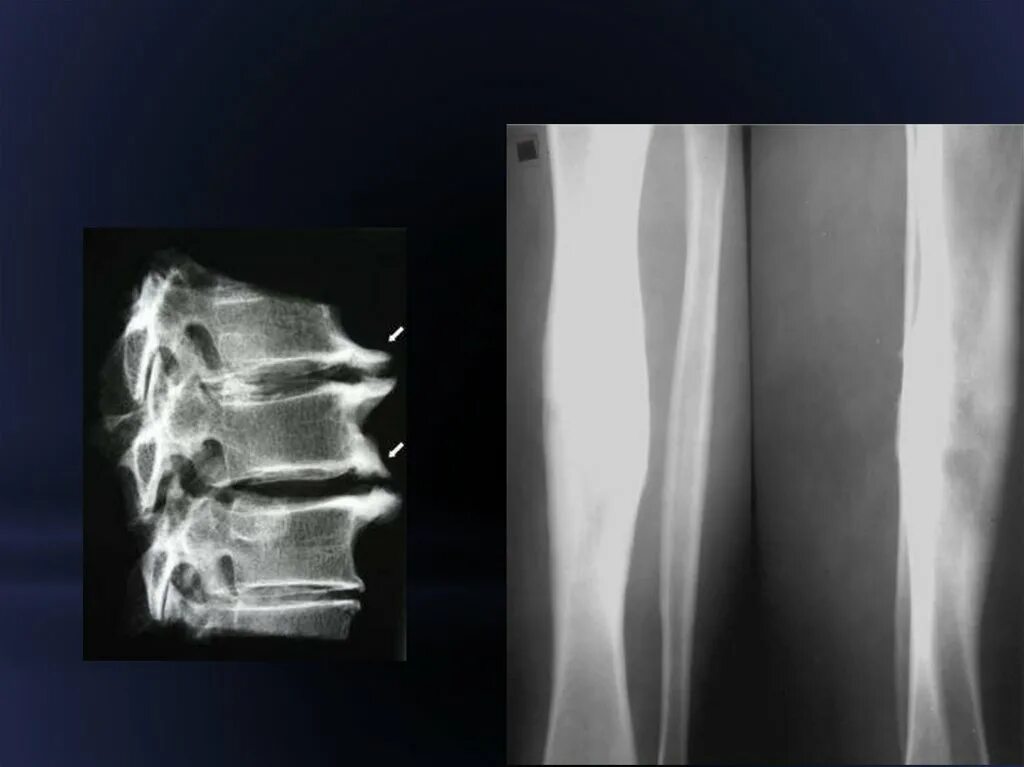

Остеосклероз симптомы